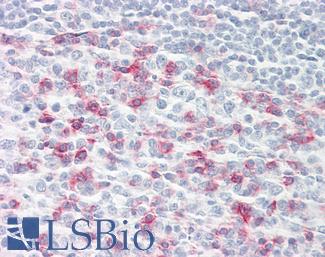

PDL1 (CD274)

Anti-B7-H1 / PD-L1 / CD274 antibody IHC staining of human testis. Immunohistochemistry of formalin-fixed, paraffin-embedded tissue after heat-induced antigen retrieval. Antibody LS-B10562 dilution 1:100.

PD1 (PDCD1 / CD279)

Anti-CD279 / PD-1 antibody IHC of human tonsil. Immunohistochemistry of formalin-fixed, paraffin-embedded tissue after heat-induced antigen retrieval. Antibody LS-B7883 dilution 20 ug/ml.